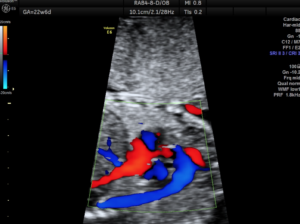

Ο έλεγχος της εμβρυϊκής καρδιάς στο δεύτερο τρίμηνο είναι πια πλήρης δηλαδή ελέγχεται τόσο η ανατομία όσο και η λειτουργία και η ανάπτυξη της εμβρυϊκής καρδιάς. Είναι εφικτό να διαγνωσθούν σχεδόν όλες οι μείζονες και οι ελάσσονες συγγενείς καρδιοπάθειες. Κατά τον προγεννητικό έλεγχο δεν δύναται να διαγνωσθούν κάποιες μυοκαρδιοπάθειες, οι καναλοπάθειες, οι ανωμαλίες των στεφανιαίων αγγείων, το μεσοκολπικό έλλειμμα, η παραμονή του βοταλλείου πόρου, οι υποβαλβιδικές στενώσεις και η μερική ανώμαλη επαναφορά των πνευμονικών φλεβών.

Η εξέταση πρέπει να γίνεται από παιδοκαρδιολόγο εξειδικευμένο στην εμβρυϊκή καρδιολογία.